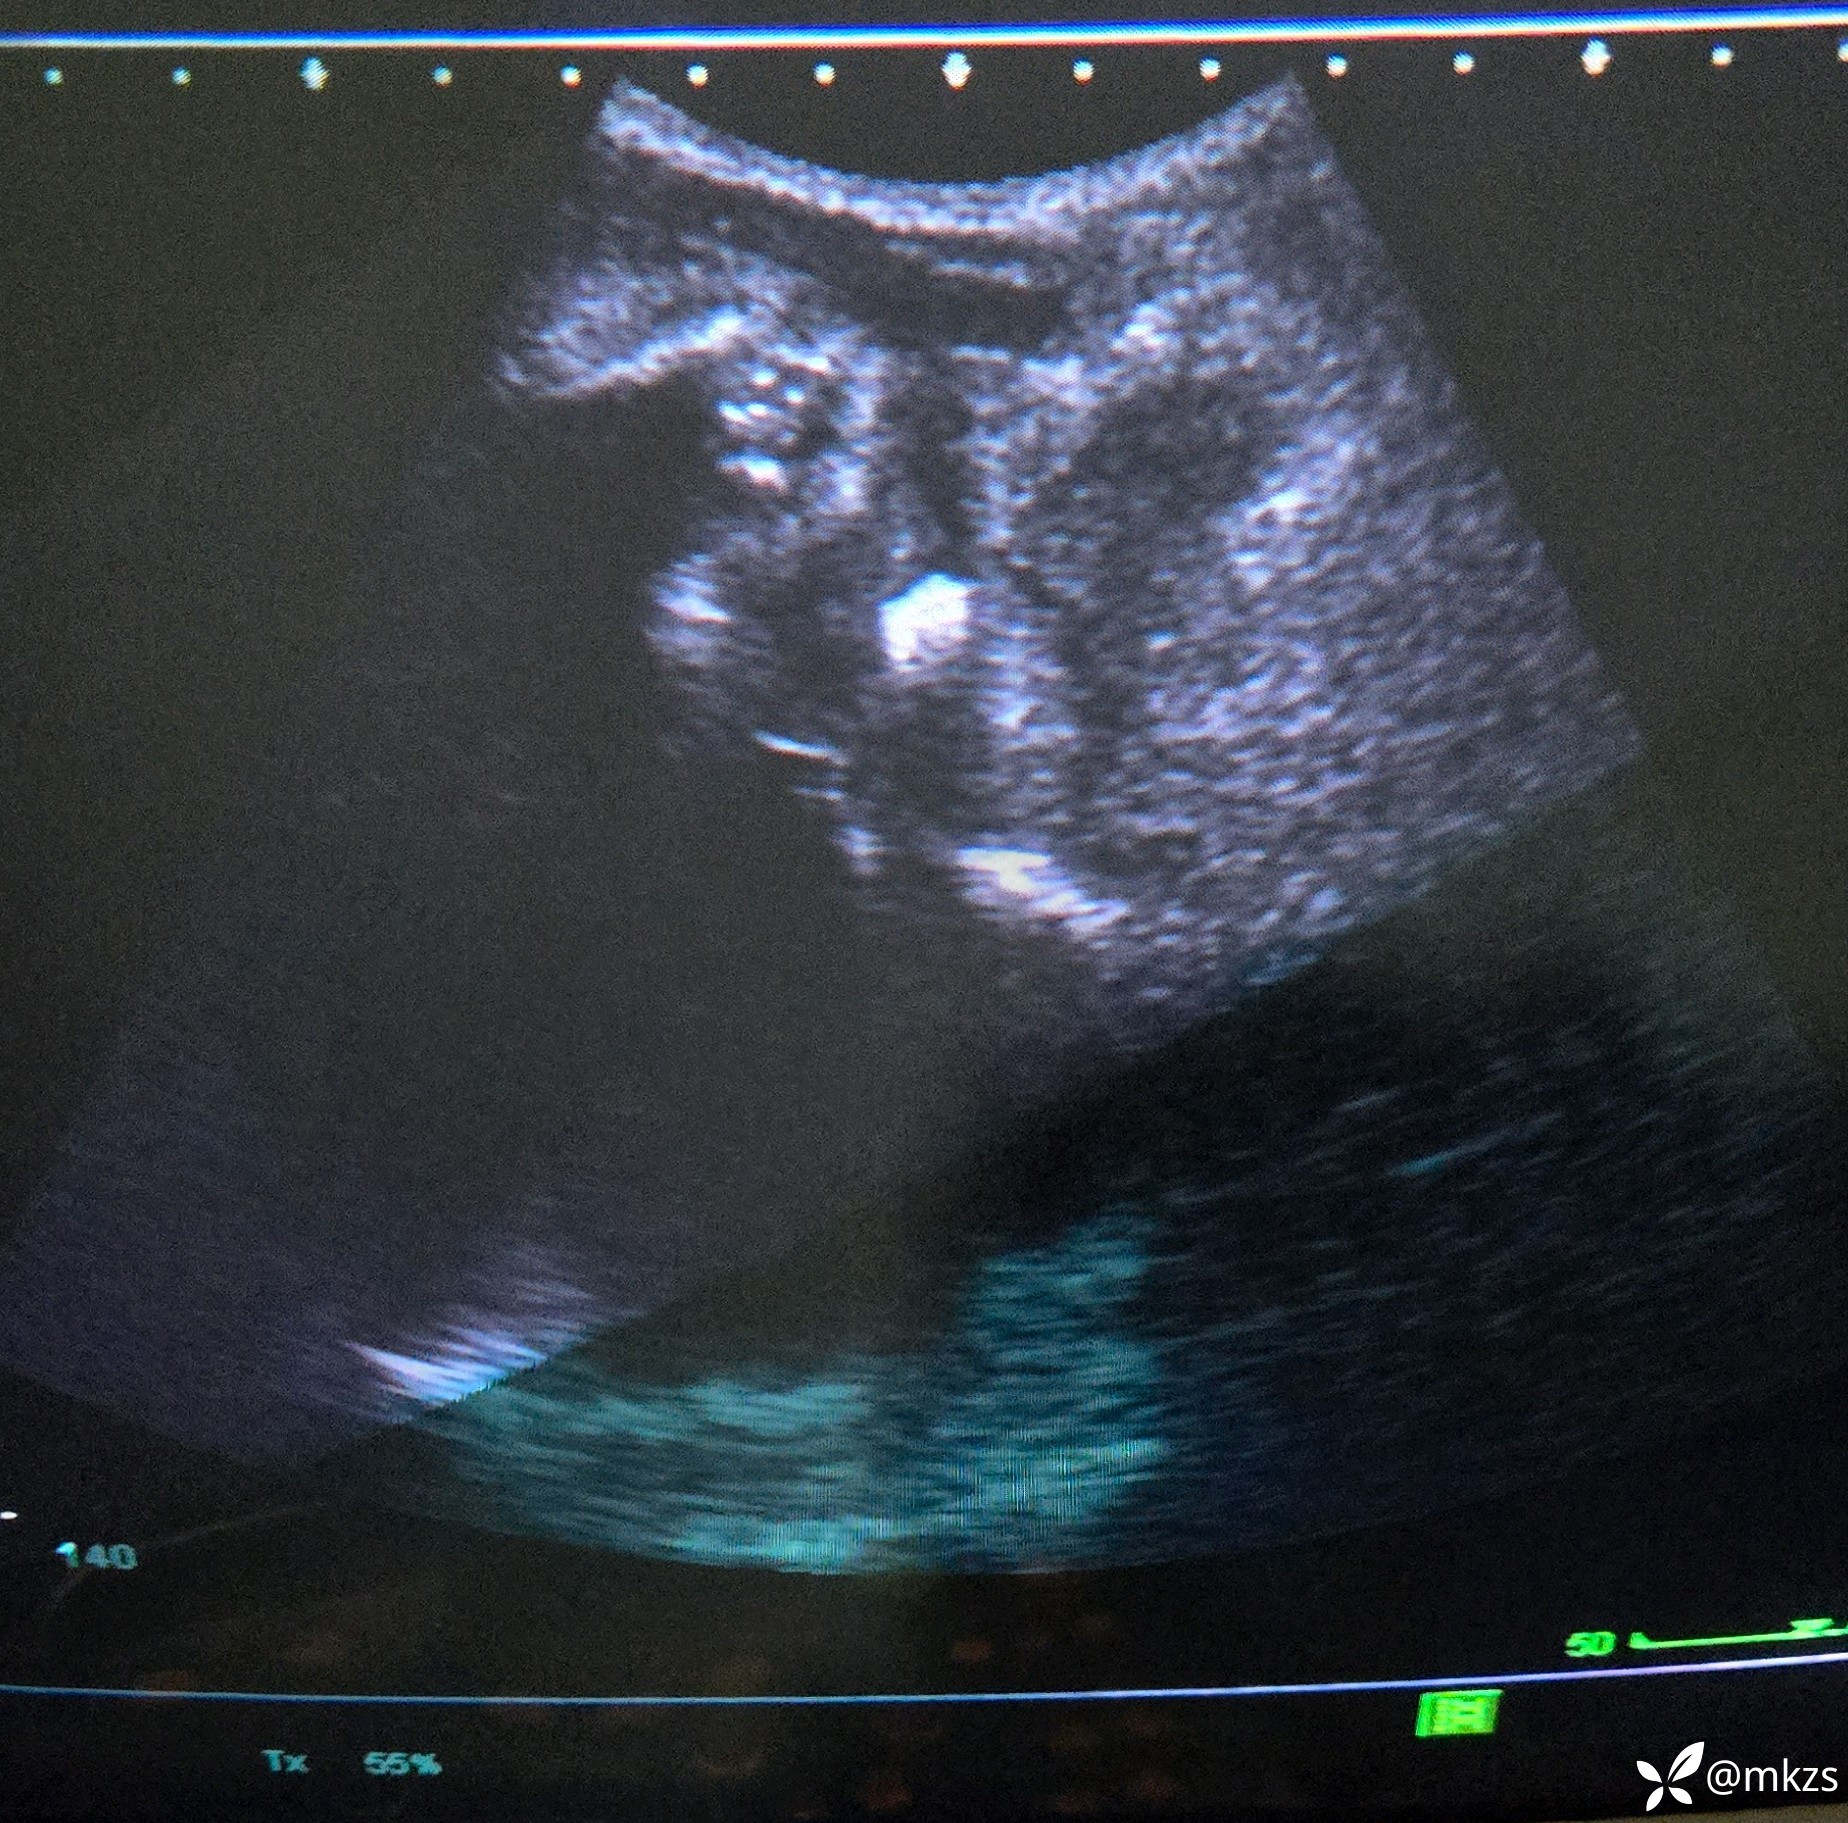

尿道结石经典病例

【检查】:b超检查会阴部

【临床诊断】:尿道结石